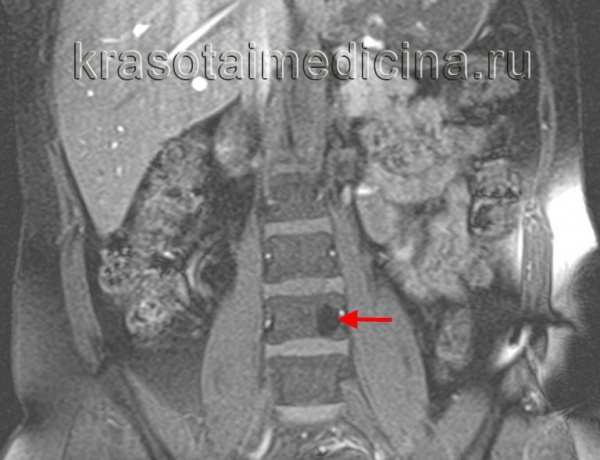

- Томография позвоночника. Для уточнения характера и степени поражения костных структур и мягких тканей после рентгенографии больного направляют на КТ или МРТ позвоночника. По данным МРТ определяется гипер- или изоинтенсивный испещренный сигнал на Т1- и Т2-взвешенных изображениях. По результатам КТ позвоночника выявляется образование с ячеистой структурой, по виду напоминающей соты.

В число рентгенологических признаков агрессивности гемангиомы позвоночника включают локализацию в промежутке между III и IX грудными позвонками, поражение всего тела, нечеткие края и расширение кортикального слоя, расширение опухоли к корню дужки. При проведении КТ и МРТ агрессивных новообразований обнаруживаются ячейки неправильной формы и мягкотканные образования в эпидуральном пространстве. Наличие трех и более из перечисленных признаков рассматривается, как свидетельство агрессивности гемангиомы позвоночника.